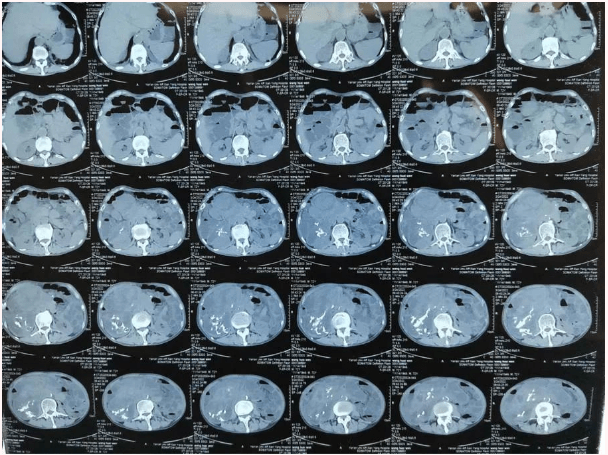

患者王大爺,男,72歲,發(fā)現(xiàn)腹腔腫物10余年,近兩年來(lái)患者雙下肢乏力、貧血,依靠間斷輸血維持著正常生活,出現(xiàn)頭昏,行動(dòng)困難,腹部疼痛及便血慕名來(lái)我院就診。入院后查體評(píng)估患者年齡大,體質(zhì)差,嚴(yán)重貧血,肺部感染及腸梗阻征象,腹部增強(qiáng)CT檢查提示腹膜后巨大腫瘤,長(zhǎng)徑超過(guò)30厘米,占據(jù)大部分腹腔,并可能存在雙原發(fā)腫瘤。

苗滿園腫瘤外科團(tuán)隊(duì)在麻醉科/手術(shù)室的緊密配合下為該患者進(jìn)行手術(shù),術(shù)中發(fā)現(xiàn)腫瘤巨大,幾乎占據(jù)了整個(gè)腹腔,從左側(cè)向右腹腔延伸,向上將肝、腎擠向膈下,向左將胃及小腸擠向左上腹,向下深達(dá)盆腔內(nèi),包繞下腔靜脈、腸系膜上動(dòng)脈等大血管及輸尿管,回盲部及回腸也受侵犯。手術(shù)難度巨大,風(fēng)險(xiǎn)極高。團(tuán)隊(duì)?wèi){借著高超的手術(shù)技能和精準(zhǔn)的手術(shù)預(yù)案沉著應(yīng)對(duì),迎難而上,應(yīng)用高頻電刀、超聲刀、切割縫合器等先進(jìn)設(shè)備,耗時(shí)近5小時(shí)為患者切除了巨大腹腔腫瘤,并聯(lián)合右半結(jié)腸切除,術(shù)中出血僅50ml。術(shù)后病理為腹膜后巨大平滑肌瘤+回腸腺癌。